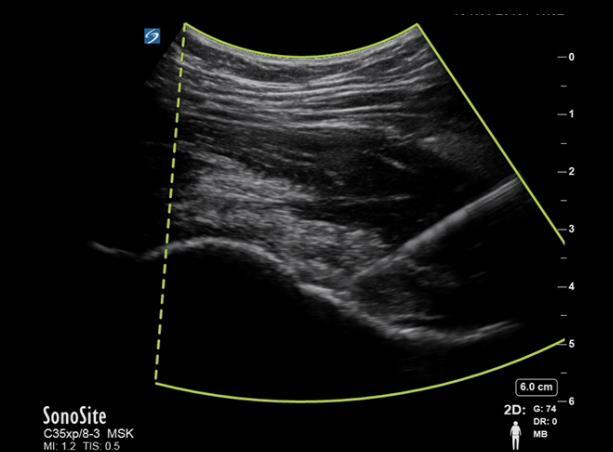

使用 C35 探头进行髋关节穿刺针注射图像